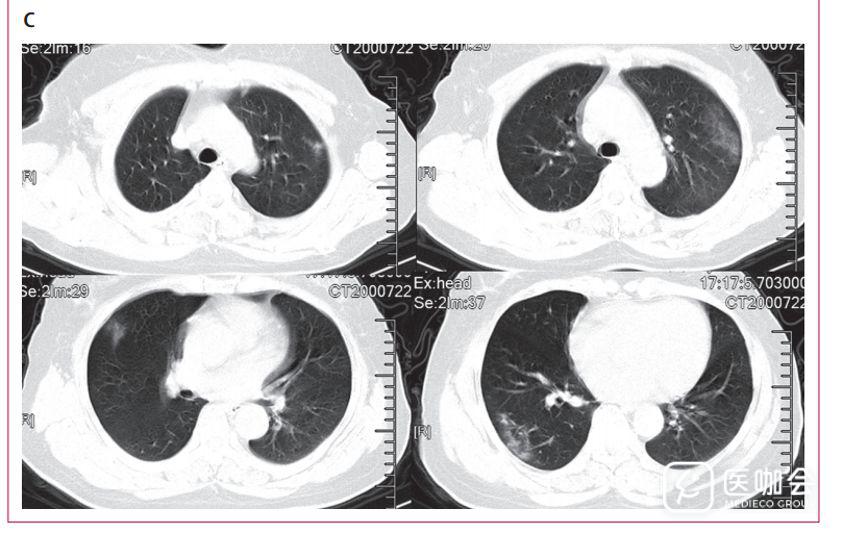

下图3是胸部CT的结果,分为ABC三张图。

A是在症状开始15天时,一位年龄40岁男性胸部横面CT显示双侧多小叶及亚段实变区。